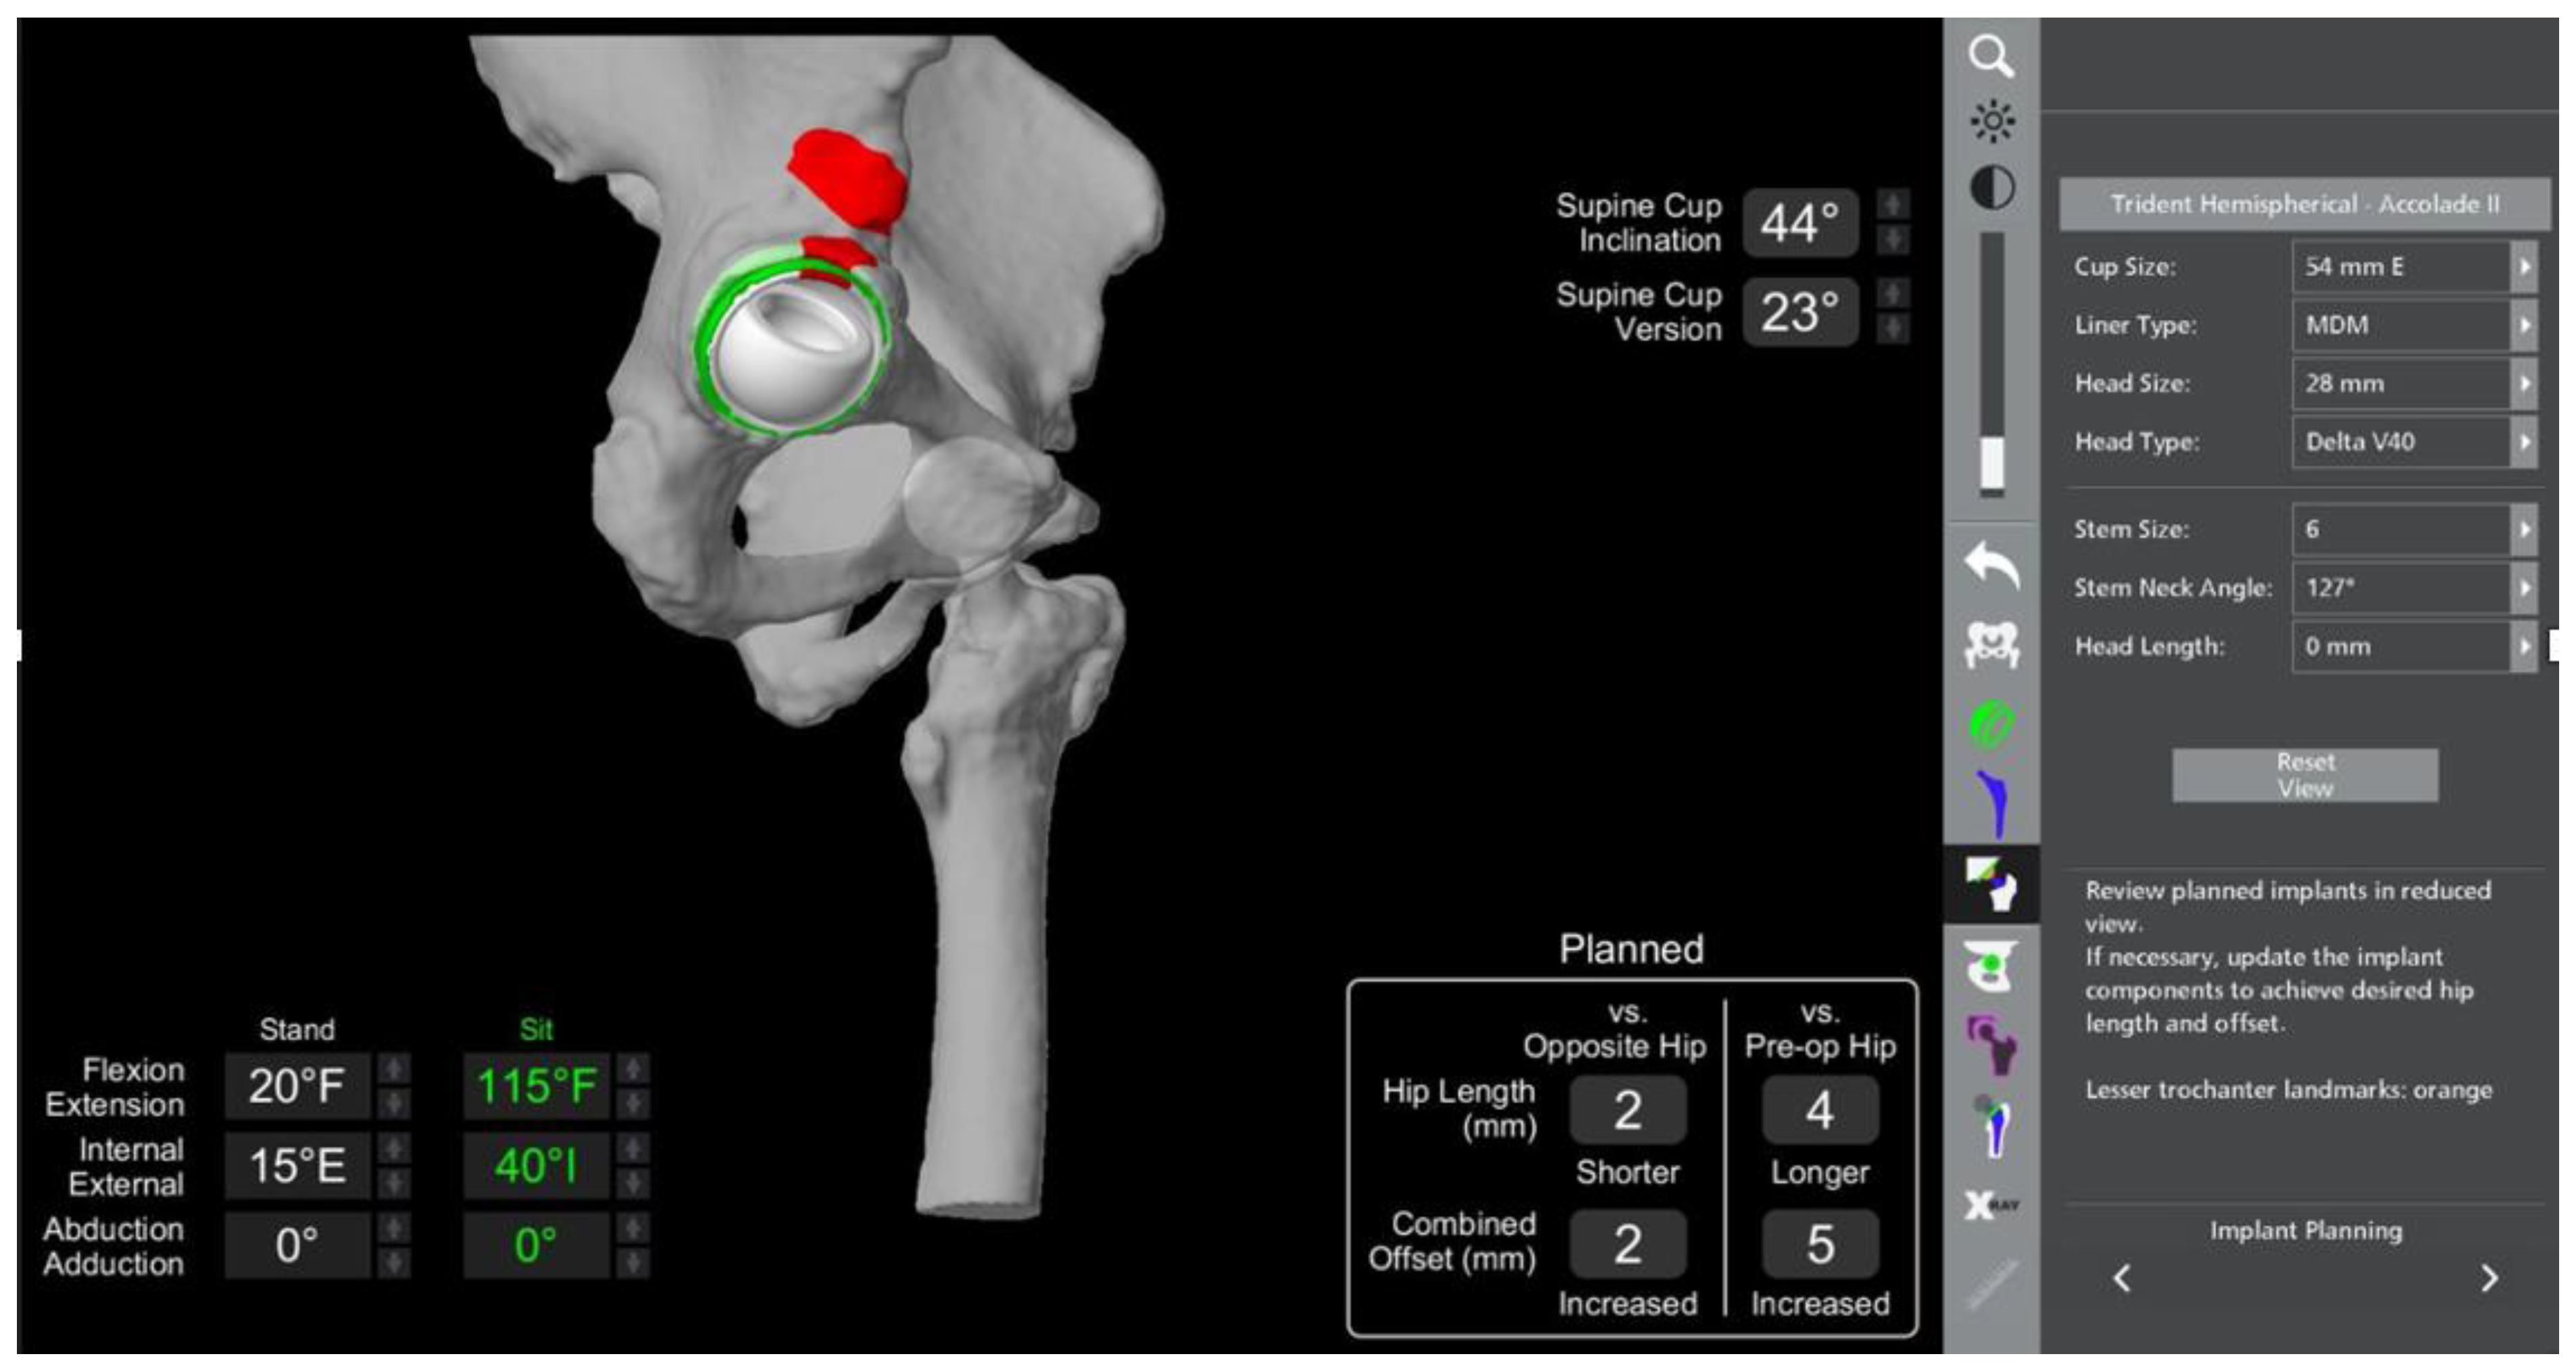

- In this case, the native femoral retroversion (−6 degrees) posed a challenge in avoiding impingement (Figure 7). Upon assessing VROM, bone-on-bone and implant-on-implant impingement in deep flexion were noted (Figure 8). Using the robotic software, the planned femoral version was corrected to +16 in the femoral broach (Figure 9a,b).

- VROM was performed again, and impingement in flexion was eliminated (Figure 10). In extension, upon subtracting the femur, it became apparent that there was a small area of impingement secondary to an anterior osteophyte which was planned to be removed after cup insertion during the operation (Figure 11a,b).